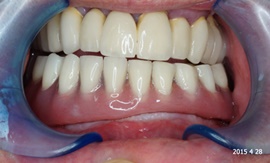

Bezzębie całkowite górne. Początkowo wykonane na mieście mosty całoceramiczne wydawały sie sukcesem, ale po roku pojawiły sie obrzęki i krwawienie z dziąseł. Pacjentka zgłosiła się do leczenia. Usunięto wszystkie zęby w szczęce. Sterowana regeneracja tkanek kości wyrostka, modelowanie kształtu i objętości tkanek miękkich, mosty porcelanowe przykręcane do implantów. Zadowalający wynik anatomiczny i estetyczny.